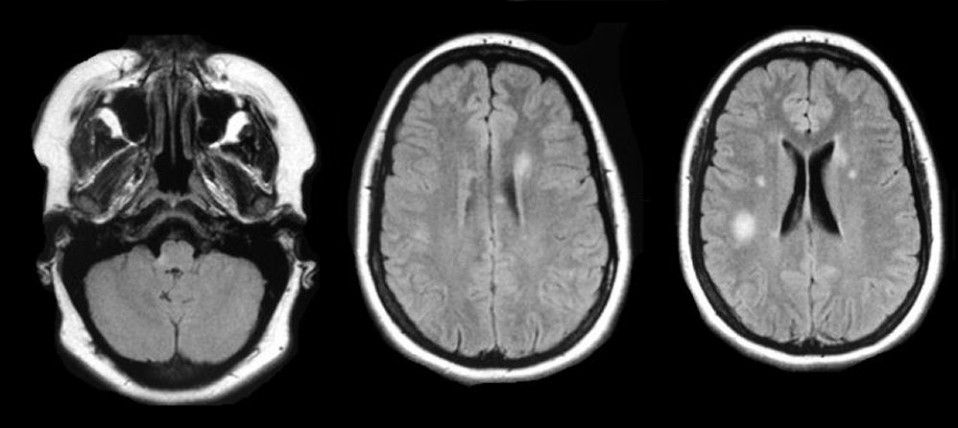

Otoimmün hastalıklar başlığı altında yer alan MS (Multiple Skleroz) beyinde ve omurilikte, mesajları taşıyan sinir telleri çevresindeki koruyucu kılıfın (miyelin kılıfı) olağan çalışmaması halinde meydana geliyor. Merkezi sinir sistemiyle organların bilgi iletişimini sağlayan omuriliğin miyelin tabakası üzerindeki fiziksel tahribatın bir sonucu olarak kendini gösteriyor.

Fare modellerinden çıkan sonuçlar, aşının MS hastalığının gelişimini engellediği ya da hastalığı erken aşamada durduğunu kanıtladı. Aynı zamanda hayvanların motor sinirlerinin işlevini geri kazandığını da ortaya koydu. Beraberinde, tedavi edilen farelerin beyin ve omuriliğinde ciddi ölçüde az sayıda proinflamatuar bağışıklık hücresi ve daha az miyelin hasarına rastlandı.

Öte yandan, bilim insanları, tedavi edilen farelerin genel bir bağışıklık bastırma belirtisi göstermediğini söyledi. Bu durum MS hastaları için mevcut bağışıklık bastırıcı tedavilerle ilişkili olumsuzlukların üstesinden gelebileceğine dair umut oldu.

MS, bağışıklık sisteminin sinir liflerini örten yağlı koruyucu kılıf olan miyeline saldırması durumunda kendini gösteriyor. Bu sebeple, MS ve diğer otoimmün hastalıklar için tedavi geliştirmedeki asıl amaç, tüm bağışıklığı baskılanmasına engel olarak miyeline saldıran hücreleri spesifik olarak etkisiz hale getirilmesi planlanıyor. Fakat MS hastalığına karşı geliştirilen tedaviler, miyeline saldıran bağışıklık hücrelerinin yanı sıra, vücudu yabancı mikrorganizmalara karşı koruyan tüm bağışıklık sistemini etkisiz kılıyor. Bu durum ise MS hastalarının bağışıklık tepkilerini bozuyor.